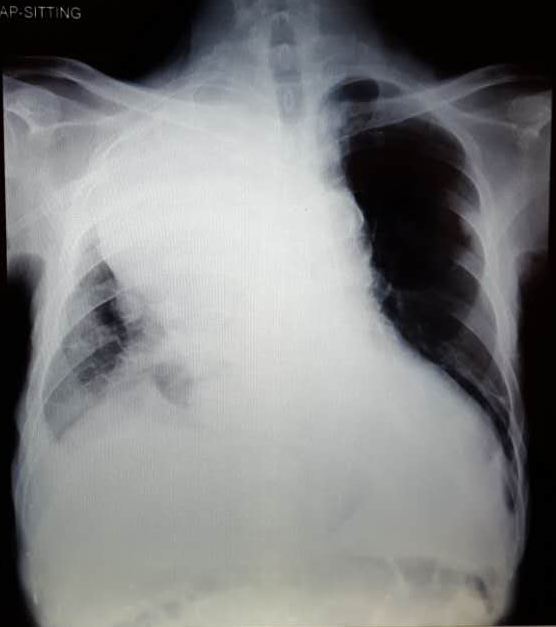

Kat and her family came to a private hospital in Penang for further management. MRI of her abdomen showed:

- a lesion in the region of bifurcation of the common bile duct. It measures 42.4 x 50.0 x 24.5 mm.

- gallbladder was grossly distended.

- Para-aortic lymph node was enlarged, measuring 52.7 x 49.0 mm.

Diagnosis: Klatskin tumour with biliary obstruction and para-aortic lymphadenopathy.